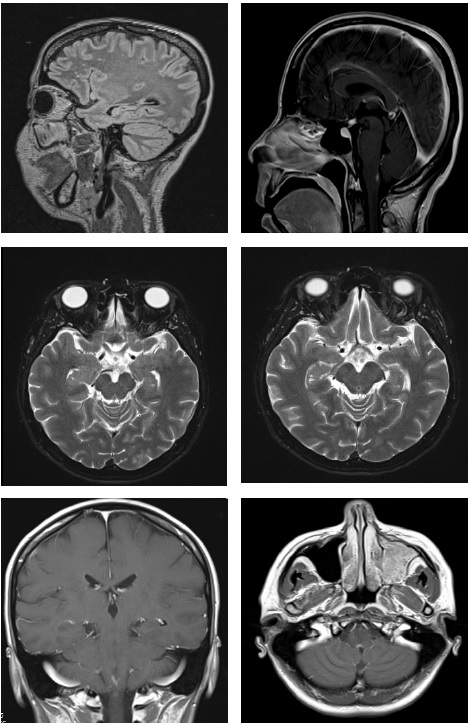

La RMN muestra lesiones hipercaptantes en hipotálamo y obex (Figura 1) descritas como lesiones inflamatorias. Como en estas áreas hay receptores de acuaporinas, el neurólogo sospecha enfermedad del espectro de la neuromielitis óptica o enfermedad de Devic, solicita anticuerpos IgG contra acuaporinas despues del estudio de las causas diferenciales más comunes, como enfermedades infecciosas, infiltrativas o autoinmunitarias. Se realizan ANAS, ENAS, ANCAS, biopsia de glándula salival, además de punción lumbar donde se toma film array, antígeno para criptococo y tinta china. También se estudiaron infecciones como VIH y Hepatitis B, con resultado negativo.

A los seis meses del inicio del tratamiento la paciente continúa con buena evolución clínica, sin síntomas, y se realiza RMN de control que muestra desaparición de las lesiones inflamatorias en el tallo y en el hipotálamo.